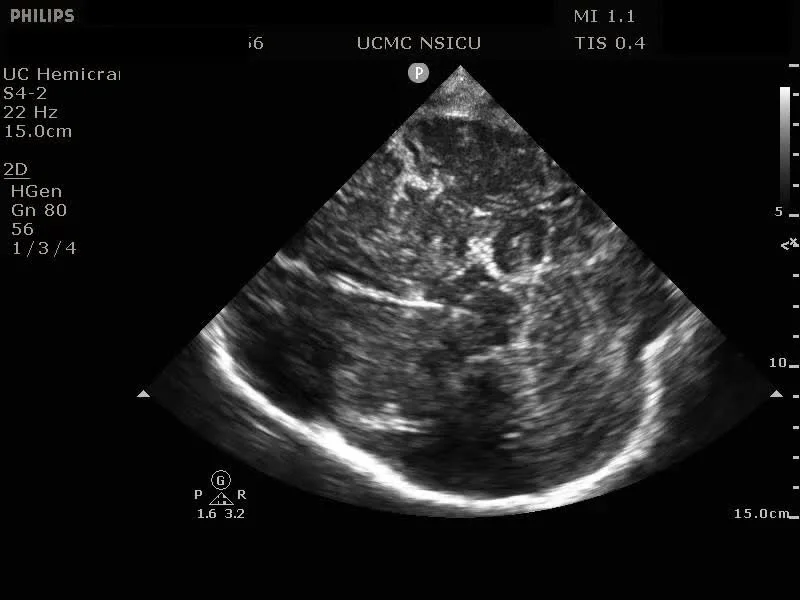

CRUSH: Cranial Ultrasound Via Hemicraniectomy

AKA Hemicraniectomy Ultrasound: Point of Care Ultrasonography (HOCUS POCUS)

Video 1: Axial view demonstrating the midbrain, collicular plate, and falx